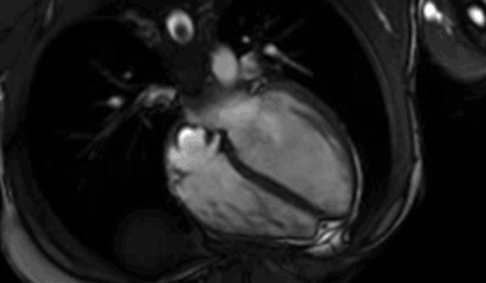

Resonancia Magnética Cardíaca

La toma de imágenes cardíacas por resonancia magnética utiliza un poderoso campo magnético, ondas de radio y una computadora para producir fotografías de las estructuras dentro del corazón. La RM cardíaca no utiliza radiación ionizante.

La RM de corazón se utiliza para evaluar la anatomía y funcionamiento de las cámaras, las válvulas, el tamaño y el flujo de sangre a través de los vasos mayores, y las estructuras circundantes del corazón tales como el pericardio (el espacio lleno de fluidos que rodea al corazón). Para diagnosticar una variedad de problemas cardiovasculares (corazón y/o vasos sanguíneos) tales como tumores, infecciones y enfermedades inflamatorias. Evaluar los efectos de la enfermedad de las arterias coronarias, como el flujo restringido de sangre hacia el músculo del corazón, y las cicatrices que quedan en el músculo del corazón luego de un ataque cardíaco. También se utiliza para planear el tratamiento de un paciente con problemas cardiovasculares, evaluar efectos de cambios quirúrgicos, y la anatomía del corazón y los vasos sanguíneos en niños y en adultos con enfermedad congénita del corazón.